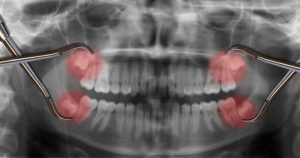

Although a dentist will always strive to do everything they can to help you keep all of your teeth, there are dozens of reasons you may need to have...